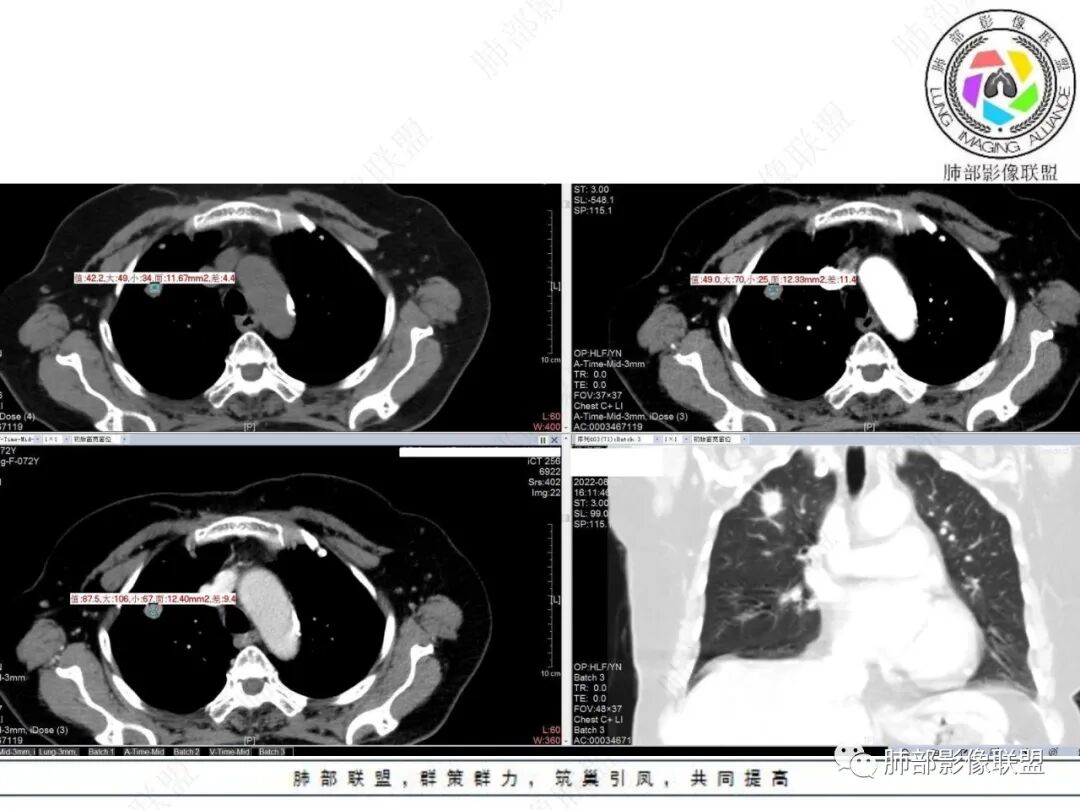

老年女性右肺上叶前段实性结节,边缘可见长短不一毛刺,临近胸膜受牵拉,中心疑似低密度影,空泡征?增强呈渐进性强化,首先考虑肺腺癌,鉴别良性肿瘤,错构瘤、PSP。

右肺上叶前段结节,边界清楚,可见浅分叶、毛刺、血管集束征及胸膜凹陷征,密度欠均匀,增强扫描渐进性明显强化,老年女性患者,体检发现,考虑腺癌,鉴别结核、慢性炎症。

右肺上叶结节看着就挺恶的,血管集束、冠状位看到一条血管弯曲,可疑空泡,周围似乎有磨玻璃?(需要薄层明确),这些征象支持腺癌。但是病灶比较明显的延迟强化、环形强化,毛刺比较长且收缩力不是太明显,炎性肉芽肿还是要考虑。

右肺上叶前段孤立性实性结节,不均匀明显延迟强化,形态不规则,位于胸膜侧见小锯齿状凸起,胸膜牵拉及兔耳侧,结节内上侧见磨破璃影,边清(需薄层确认),另见血进入结节,邻近血管集束征,结节外侧见指状凸起影(恶性多见),定恶性,腺Ca;鉴别炎性肉芽肿,结合肺肿瘤指标抗原检查,经皮肺穿刺活检!

支持恶性结节,腺癌可能。右肺上叶尖段实性结节,边缘分叶、毛刺,与胸膜面数条牵拉线伴磨玻璃感(淋巴回流障碍),内隐约见支气管进入是否堵塞需要薄层重建。增强后静脉期中等强化。

老年女性,体检发现,无呼吸道症状。右肺上叶尖段孤立性实性结节,下份见空泡,余密度较均匀。病灶形态不规则,边缘多膨隆,可见浅分叶及细毛刺,血管集束,未能显示相关支气管情况。病灶胸膜侧见小锯齿状凸起、胸膜牵拉及兔耳征,结节前缘见磨玻璃影,磨玻璃影边界较清楚(需薄层确认),结节外侧见指状凸起影。未见卫星病灶,纵隔窗未见明显钙化。增强扫描:较明显渐进性强化。

2.病例分析:

老年女性,右肺上叶孤立实性结节,边缘欠光整,强化明显,未见卫星灶,已经让人高度警惕恶性肿瘤,尤其是腺癌!

浸润性腺癌支持点还有空泡及磨玻璃晕,但非薄层图像,磨玻璃影表现可靠性降低。

病灶张力不高,磨玻璃晕等需要鉴别隐球菌感染或其他炎性肉芽肿,虽然位置并不靠近胸膜。肺腺癌与隐球菌感染的鉴别,在影像学上也许是个永恒的话题。

没有卫星灶,没有树芽征,没有新旧不等,强化明显等不支持继发性肺结核。结节影边界欠光整,缺乏游离感,没有脂肪密度或钙化,强化特点等都未能显示出硬化性肺细胞瘤或者错构瘤的影像学特点。